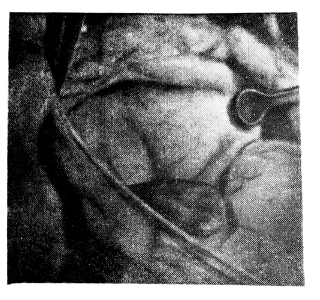

Манипуляции по выделению бронхов, сосудов под контролем трансиллюминации облегчаются, возникает четкая дифференцировка фасций, увеличенных лимфатических узлов и стенки бронха. При доступе через кава-аортальный промежуток под контролем просвечивания производится рассечение задней стенки перикарда и выделение трахеобронхиальных углов (рис. 3). При этом отчетливо обрисовываются сосуды разного калибра и возможен превентивный гемостаз. В этих же условиях облегчается выявление патологии стенки бронха в разных слоях. Метод был испытан, а затем стал систематически применяться при трансперикардиалыюм доступе к главным бронхам в хирургической клинике (зав. — действ, член АМН СССР проф. Л. К. Богуш) Центрального института туберкулеза М3 СССР. Оперирование под контролем трансиллюминации в указанной области становится более безопасным, сокращается время вмешательства.

Рис. 3. Выделенный через аорто-кавальный промежуток правый трахеобронхиальный угол и

область бифуркации трахеи в проходящем свете. Интенсивные затенения лимфатические узлы.